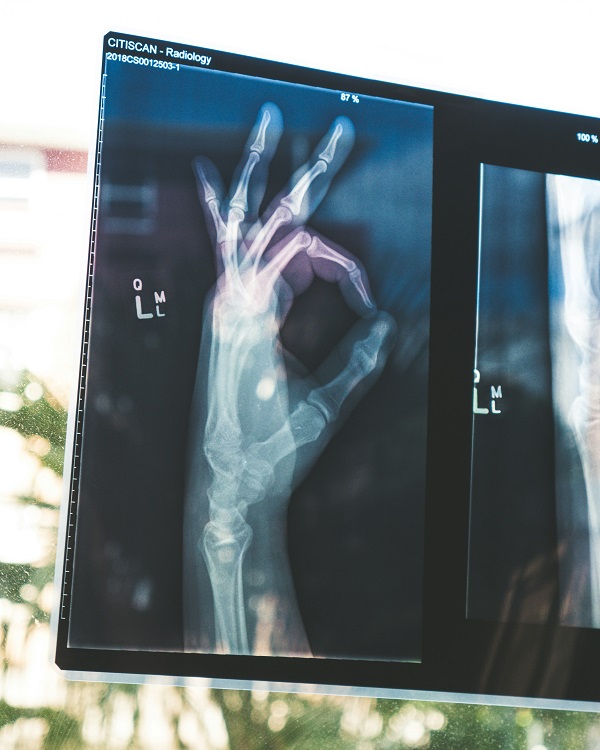

From radiologic technologists capturing vital images, physiotherapists restoring movements of a patient to medical lab technologists decoding the language of blood and cells — all are artisans of applied science and healing. The flawless capturing of MRI scans, monitoring of heart rhythms with precision equipment, or speech gently nurtured back to fluency after a trauma — are made possible by the expertise and experience of allied health sciences professionals.